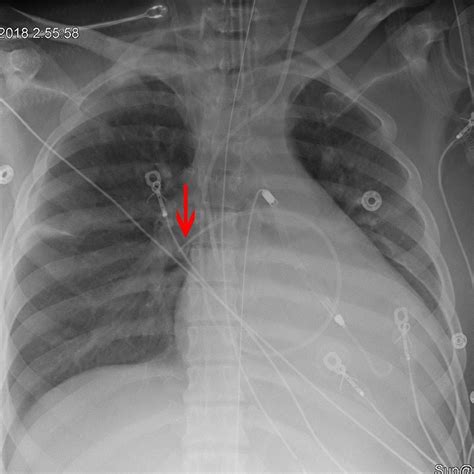

• swan ganz catheter xray

• swan ganz catheter cxr

The insertion of a Swan Ganz catheter is performed under sterile conditions, usually guided by ultrasound to minimize venous trauma. The catheter is passed through the right side of the heart, with pressure waveforms monitored continuously on a display monitor to verify correct positioning at each step. Once in the pulmonary artery, the balloon is briefly inflated to obtain the wedge pressure reading. Maintaining accurate calibration and preventing air embolisms are critical steps in the procedure.

Continuous monitoring is essential after placement. Nurses and intensivists must regularly check the catheter position, ensure that the transducer is properly leveled and zeroed, and observe for potential complications like thrombosis or infection at the insertion site.